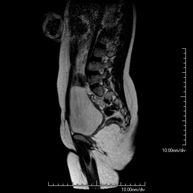

- Spinal column

- Lumbar spine MRI

This non-invasive diagnostic procedure uses an electromagnetic field and radio waves (from a transmitter and receiver) to acquire high-definition anatomical images of the lumbar and sacral regions. It is a radiation-free procedure. Indicated for: trauma, sciatica, herniated discs, tumours, infections.

- Sacrum-coccyx MRI

This non-invasive diagnostic procedure uses an electromagnetic field and radio waves (from a transmitter and receiver) to acquire high-definition anatomical images of the sacrum and coccyx. It is a radiation-free procedure. Indicated for: sacrococcygeal pain, trauma.